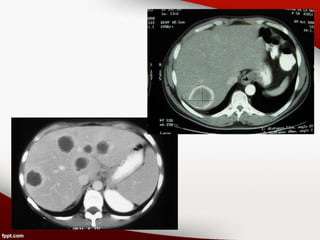

Hallazgos radiológicos

• ECOGRAFÍA: existen zonas hiperecógenas o

hipoecógenas heterogéneas mal definidas que

van tomando el aspecto de COLECCIÓN con

refuerzo posterior.

• TOMOGRAFÍA COMPUTADA: la lesión

hipodensa se halla rodeada por una envoltura

más o menos gruesa que se realza claramente